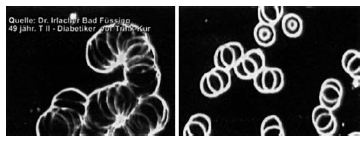

Рис. 16. На левой фотографии вы видите кровь больного с многочисленными кристаллами мочевой кислоты. На правой фотографии — кровь того же больного через три дня приема живой воды: исчезновение кристаллов мочевой кислоты. Источник: статья доктора Ирлахера в журнале альтернативной медицины «CoMed».

Иллюстрация к книге — Живая и мертвая вода — совершенное лекарство [i_003.jpg]